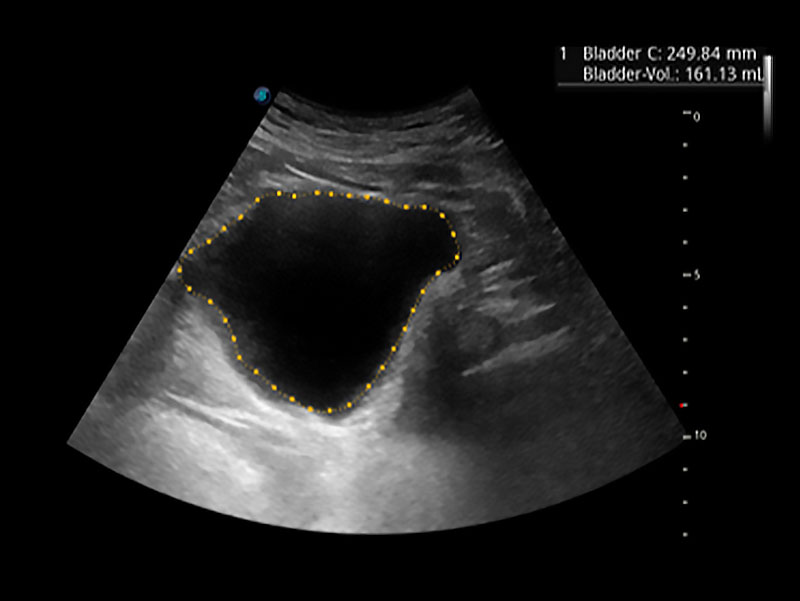

一键自动识别膀胱壁及自动测量膀胱容积,不受膀胱形状和大小的限制,帮助医生快速精准获得测量的数据。